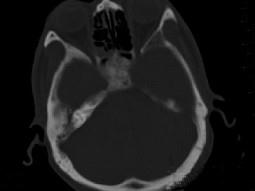

问题 男性,56岁,鼻咽癌放疗后复查,CT扫描如图所示,请选择正确的答案 ( )

选项 A、放疗后骨炎 B、骨瘤 C、骨结核 D、致密性骨炎 E、化脓性骨髓炎

答案 A